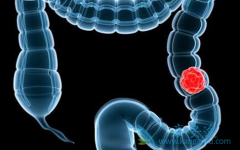

�����о������ʾ�������еĽ�ֱ���������У�����50%�Ļ������ս���չΪת���Խ�ֱ������mCRC���������ڹ�ȥ��10���У�CRA��ϵͳ����ȡ���˽ϴ��չ������ҩ���������ἰ���뻯����������������ת���Խ�ֱ�������ߵ������棬��������һ����Ⱥ�������档 �� ...

���� ������ ��REGORAFENIB�����й��Ѿ����У��������Ʋ�ֹһ�ְ�֢��ȡ���˺ܺõ���Ч������Ҫע�������ȷ������������ܽ�����Ч���ӵ���á��ǻ��߸������ȷ�����������أ���������˵��˵�ϣ��Ƽ�������160mg��Ҳ����4Ƭ��ÿ�չ̶�ʱ��һ�Σ�28 ...